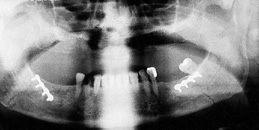

Osteosynthesis procedures are performed at our clinic according to modern international standards. Mini and micro plates made of titanium and special medical steel are used to stabilize the fractured bones. Especially for the treatment of temporomandibular joint fractures a joint plate was developed in our clinic. The development and application of resorbable osteosynthesis materials is at the same time a research task of the clinic.